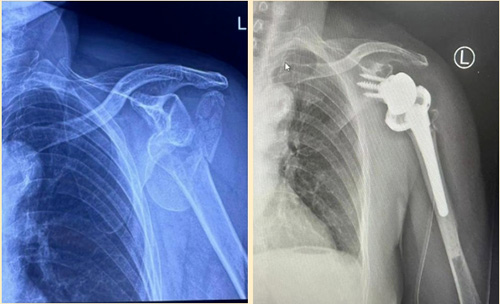

在春节假期期间,山东许多城市又迎来了一场降雪。家住临沂的张大娘因雪天路滑,不小心摔伤导致肱骨近端粉碎性骨折,慕名来到山东第一医科大学附属省立医院(山东省立医院)创伤中心就诊。创伤中心李连欣主任团队为大娘进行反式肩关节置换手术,术后恢复良好,术后左肩功能良好,李大娘及其家人对手术效果非常满意。今天,李连欣主任特别提示,瑞雪为节日增添了浓厚的喜庆氛围,给人们带来了惊喜和欢乐,但对老年人而言却增加了摔倒的风险,下雪天需警惕“雪天骨折”。

肱骨近端骨折是指肱骨靠近肩关节的部分发生骨折,最常见于老年骨质疏松患者,尤其是女性。流行病研究表明:在肱骨近端骨折人群中,60岁以上的患者占70%。骨折后的通常表现为上臂近端的肿胀、疼痛以及肩关节活动受限等症状,可能伴有血管、神经损伤以及后期肱骨头缺血性坏死等并发症。

如果是一些发生在肩关节内部的骨折或者是有比较严重粉碎的骨折,在此时必须要进行手术治疗。因为此时通过保守治疗的话,往往达不到复位的要求,并且在复位之后容易移位。另外像这种严重的骨折,如果治疗不当,并发症发生率极高,远期容易出现创伤性关节炎、关节僵硬等。常用的手术方式固定包括钢板、髓内钉及关节置换。